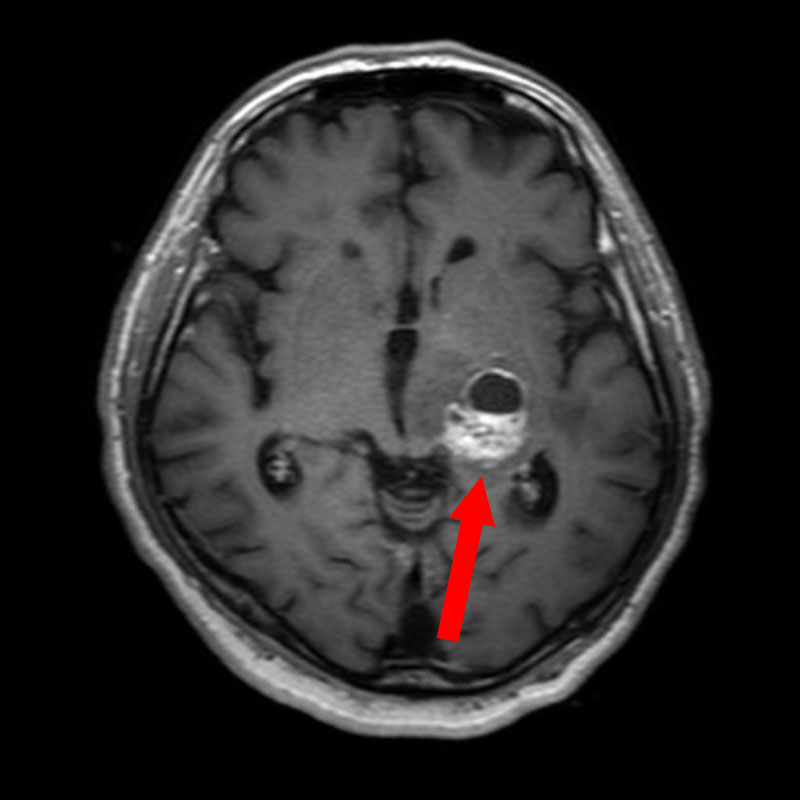

No.’25_108 手術前1

No.’25_108 手術前2